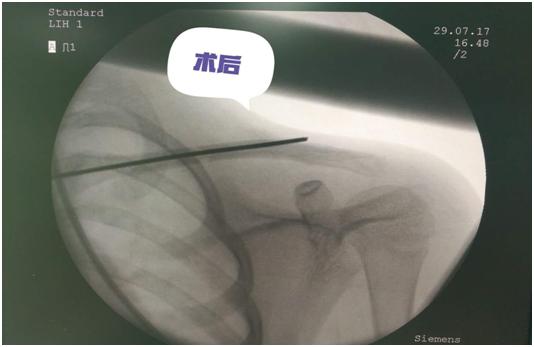

双侧股骨干骨折术后照片

锁骨干骨折术前照片

锁骨干骨折术后照片